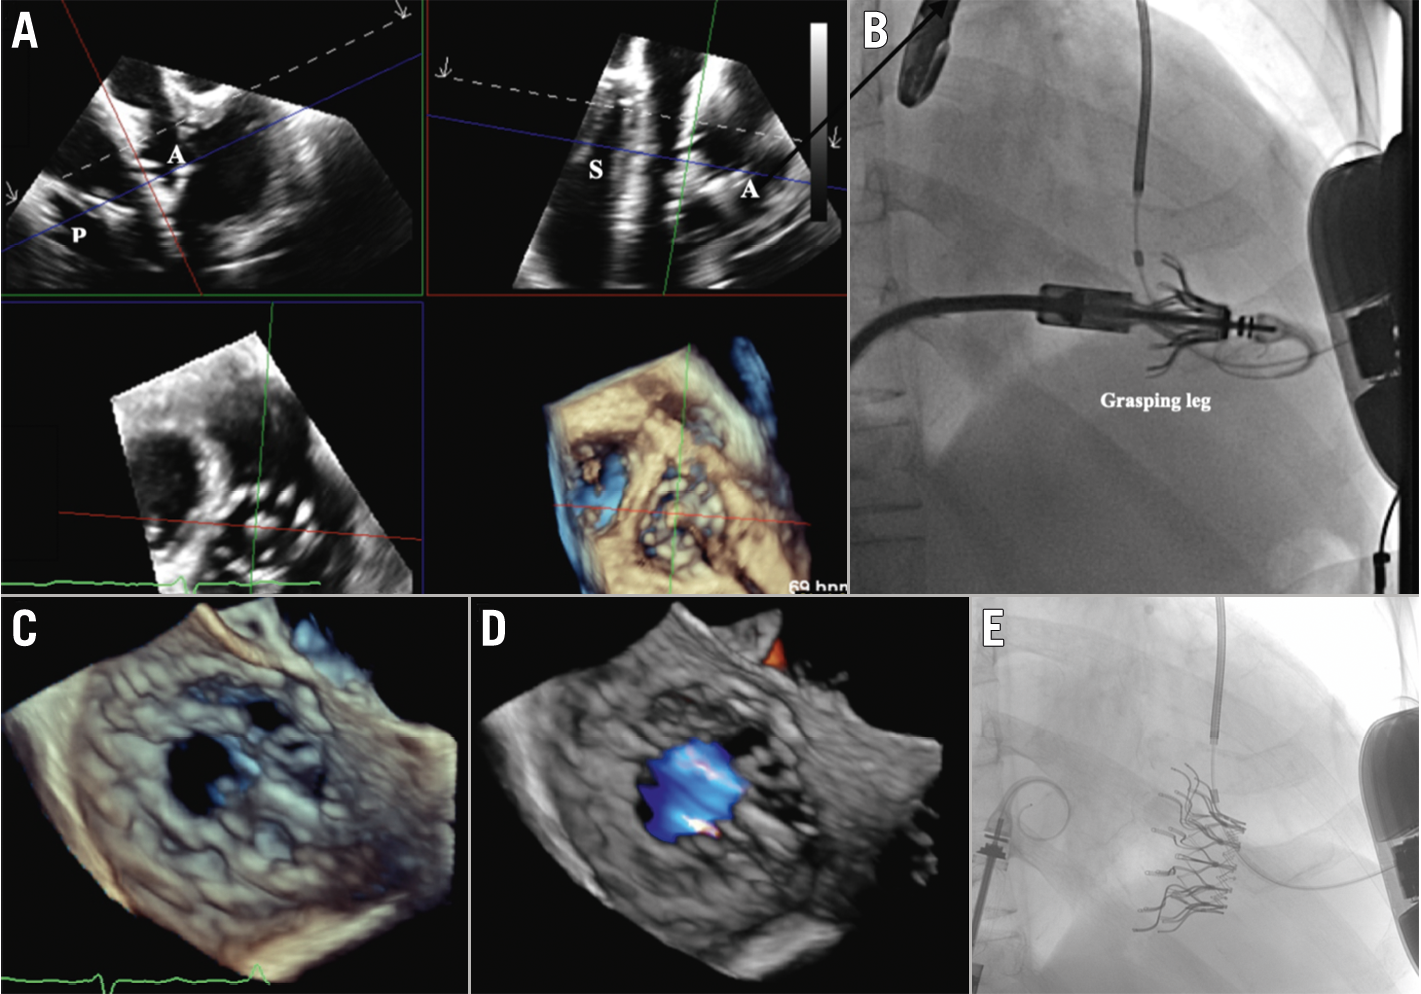

Cardiovalve TTVR was performed under general anaesthesia with TOE guidance. Following right femoral venous access, a 24 Fr sheath was inserted. A medium curl Agilis steerable catheter (Abbott) was positioned at the right atrium to pass a 6 Fr pigtail catheter through to the right ventricular apex and then exchanged for a Safari XS guidewire (Boston Scientific). Afterwards, a 30 mm Coda Balloon Catheter (Cook Medical) was gently moved back and forth from the right atrium to the RV to ensure the guidewire trajectory was free of chordae entrapment (Supplementary Figure 2, Moving image 2). The 32 Fr Cardiovalve XL device was then inserted over the Safari wire. The atrial capsule was steered to the best coaxial and concentric position to the TV under TOE guidance whilst keeping the distal edge of the atrial capsule above the native valve leaflets (Supplementary Figure 3, Moving image 3). Then the atrial capsule was retracted to expose the grasping legs by rotating the atrial capsule knob clockwise (Figure 1A–Figure 1B, Moving image 4). The system was then advanced across the TV and retracted to engage the leaflets. After confirming all ventricular legs were beneath the leaflets and engaged with the annulus at the same level under three-dimensional TOE multiplanar reconstruction, the atrial flange and ventricular portion of the Cardiovalve were sequentially deployed (Figure 1C–Figure 1D–Figure 1E, Moving image 5). Follow-up TOE the next day showed trivial PVL only, with slightly worsened right ventricular function (RV ejection fraction 39%, trace tricuspid regurgitation with a mean gradient 2-3 mmHg).

Figure 1. Cardiovalve implantation for tricuspid valve regurgitation. A) Multiplanar transoesophageal echocardiograms showing the 12 grasping legs (GL) exposed by retracting the atrial capsule. B) The exposed GL of Cardiovalve TTVR under fluoroscopy. Successful deployment of Cardiovalve TTVR under transoesophageal echocardiography (C & D) and fluoroscopic guidance (E). A: anterior; P: posterior; S: septal; TTVR: transcatheter tricuspid valve replacement